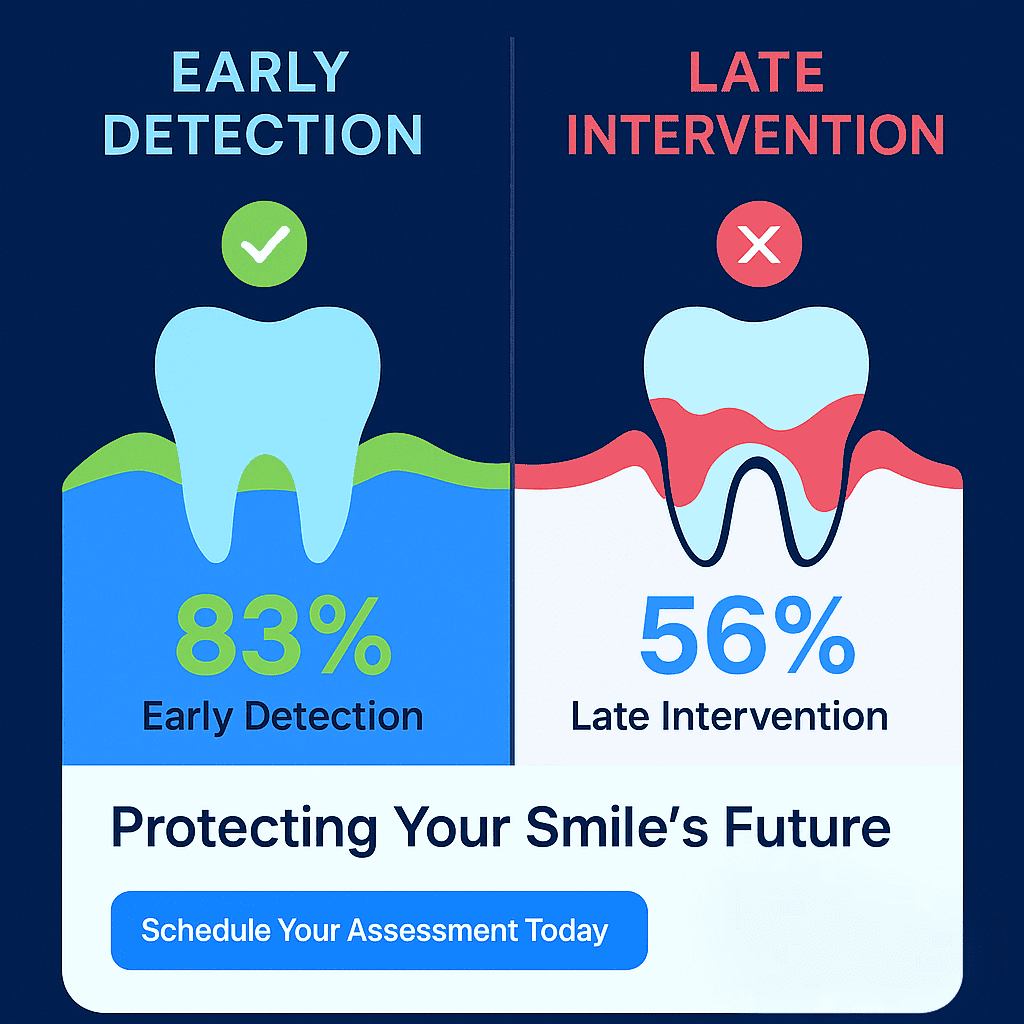

When you ignore early warning signs, here’s the progression that typically unfolds:

Stage 1: The “It’s Probably Nothing“ Phase Your gums bleed occasionally when you brush. Maybe they’re a little puffy. You think, “I probably just brushed too hard.” This is gingivitis – and it’s completely reversible at this stage. But most people shrug it off.

Stage 2: The “Getting Worse“ Phase Now your gums are pulling away from your teeth. You notice your teeth looking longer. Bad breath becomes a constant companion. You’re entering periodontitis territory, where permanent damage begins.

Stage 3: The “Oh No” Phase Teeth start feeling loose. Chewing becomes uncomfortable. You might even notice pus around your gum line. At this point, you’re looking at potential tooth loss.

The Good News: It’s Not Too Late

Here’s what I want you to understand: at almost any stage, we can help. Even if you’ve been ignoring the signs for years, modern periodontal treatment can:

- The key is acting now, not later.

If you’re reading this and thinking, “This sounds like me,” don’t wait another day. Those symptoms aren’t going to improve on their own – they only get worse.

The best time to address gum disease was at the first sign of bleeding. The second-best time is right now.